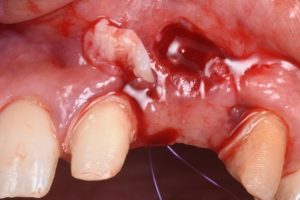

The procedure demonstrates the use of a horizontal vestibular incision with tunneling to mobilize the soft tissues and elevate the papillae. An autogenous connective tissue graft (CTG) harvested from the palate and maxillary tuberosity is utilized to augment tissue thickness. Additionally, a xenogenic bone graft is placed over the crestal area to serve as a space-maintaining scaffold and support vertical tissue stability.

Advanced flap advancement and suturing techniques are highlighted to ensure graft stability and optimal soft tissue outcomes.